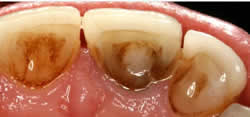

• Caries – If caries ‘decay’ is left it will travel through the enamel and dentine down into the pulp chamber.

• Your dentist has to gain access to the pulp chambers, this is done by drilling a hole in the top of your tooth.

• Once access has been gained to the pulp chambers the dead pulp is removed from the root canals using very small files and a hydrochloric wash. An additional x-ray will be taken at this point.